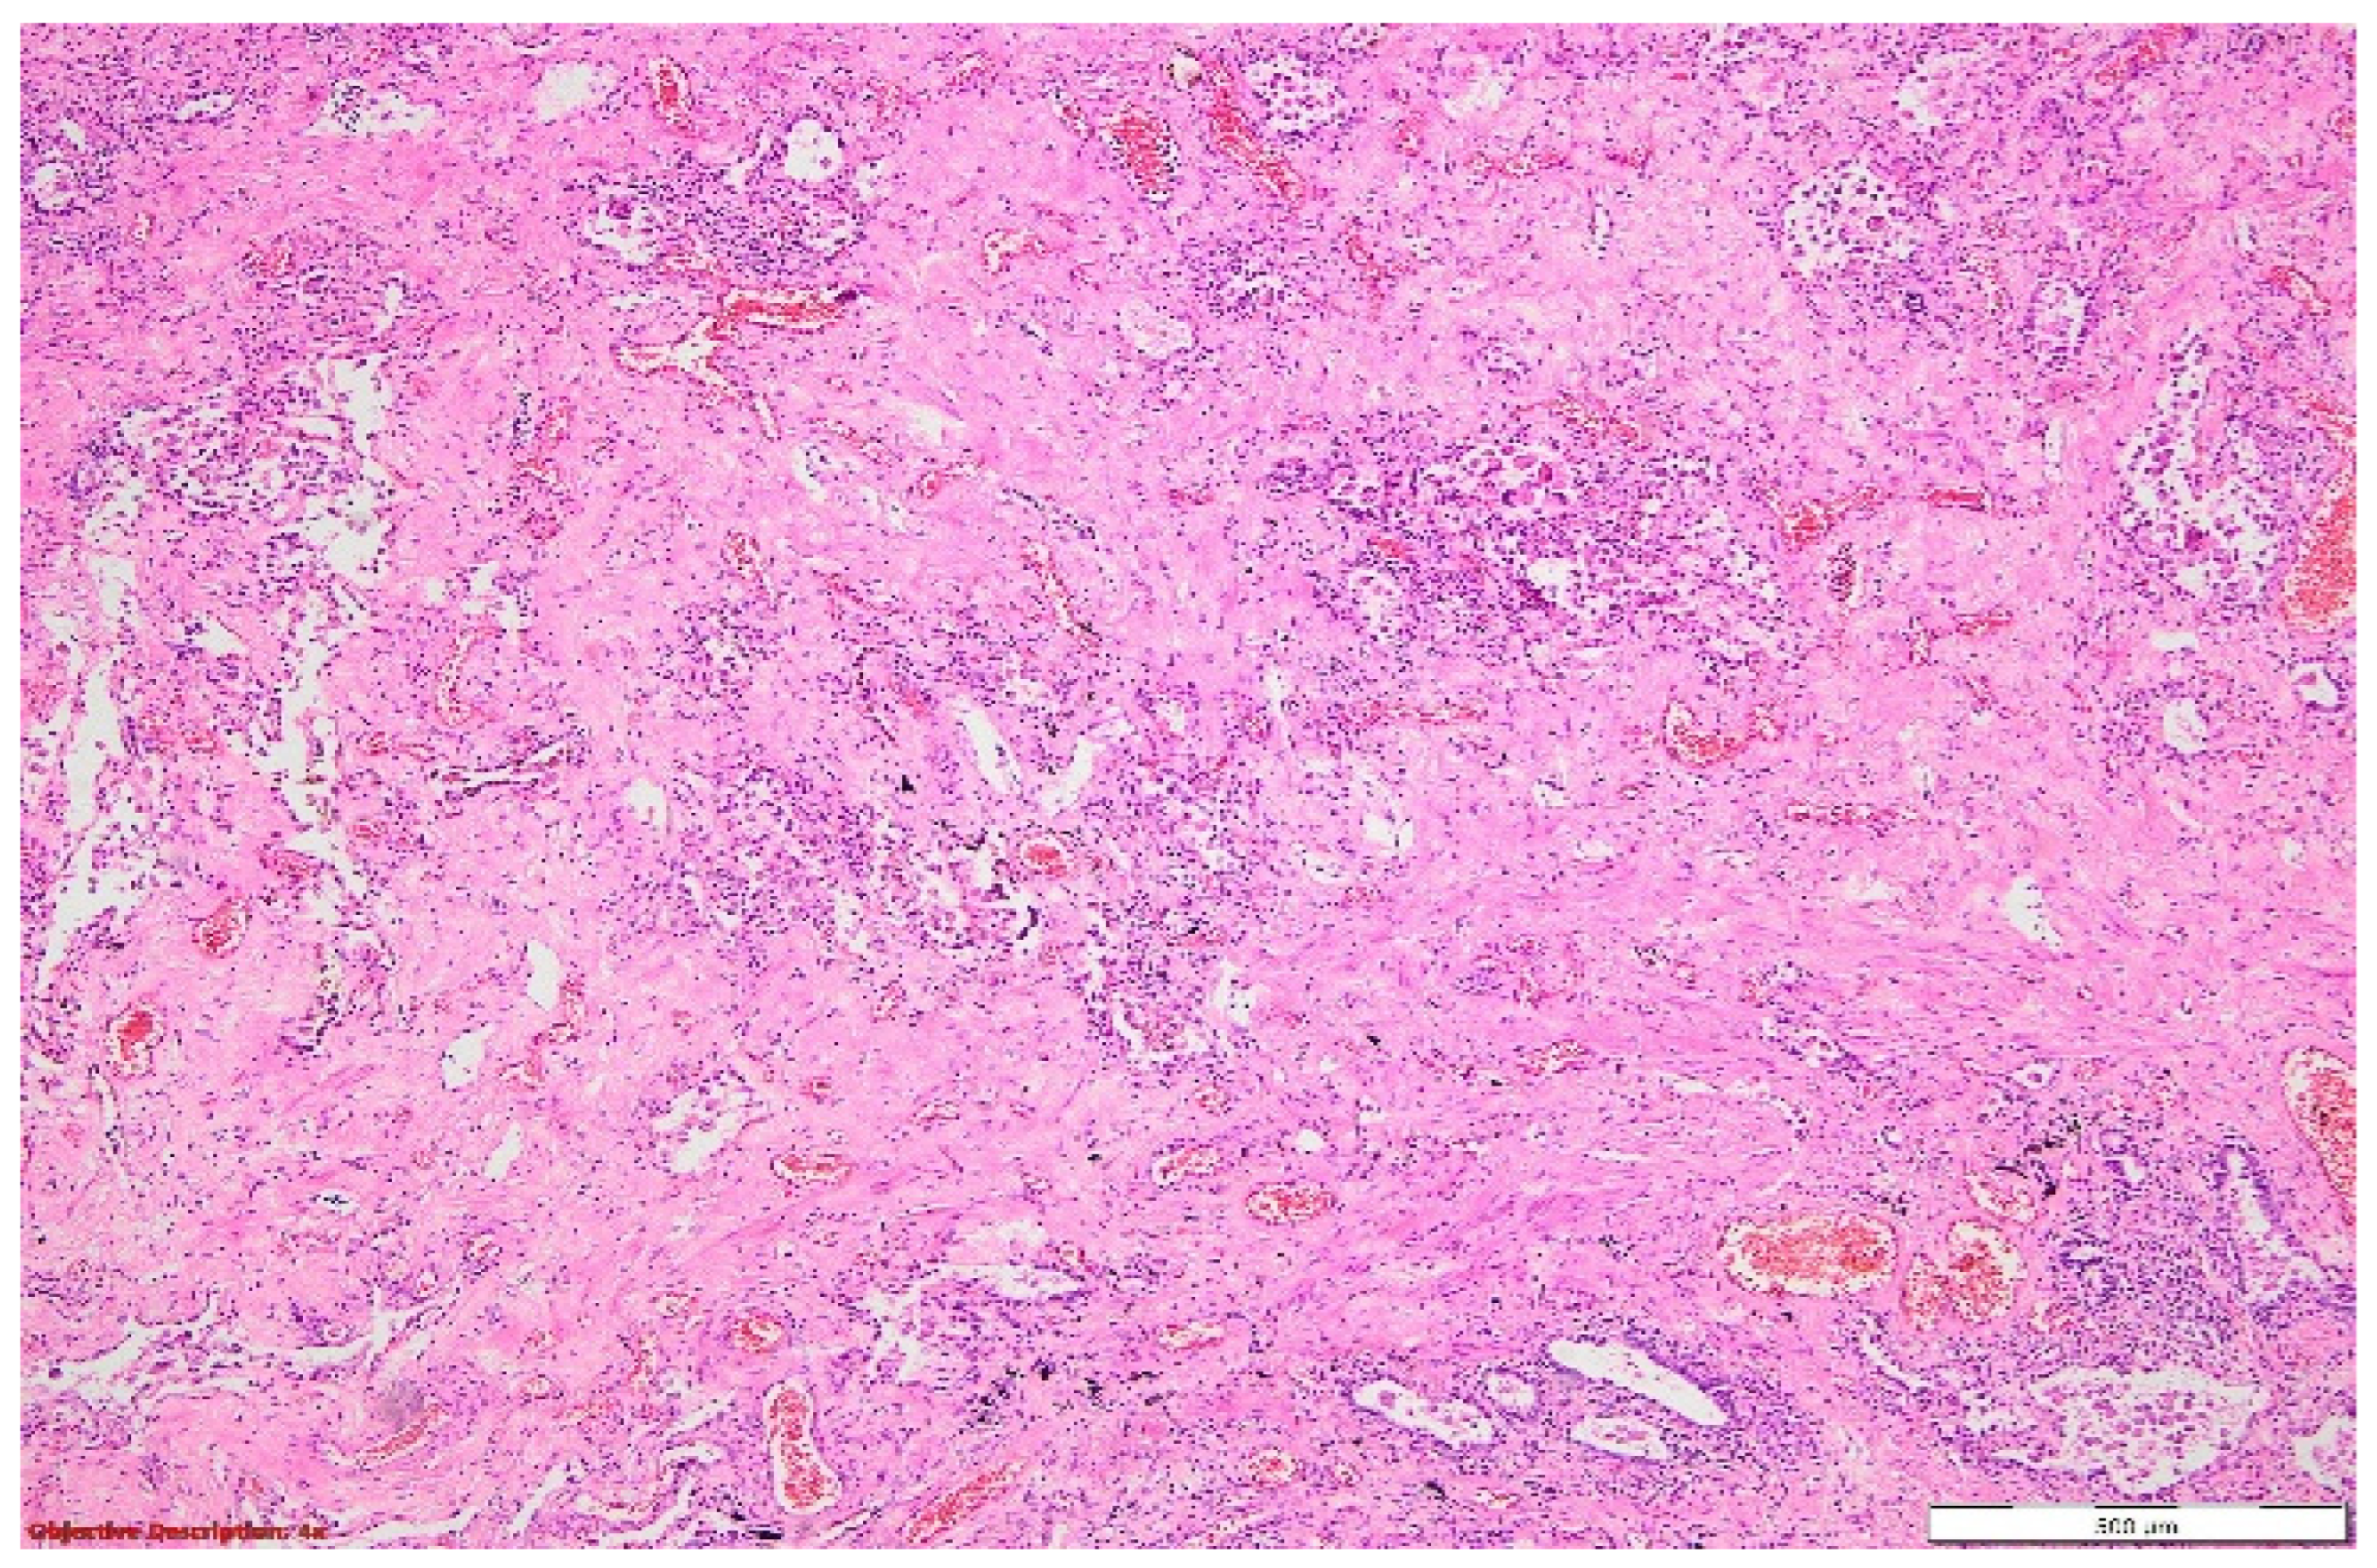

Figure 9. Lung tissue with architectural distortion, enlarged interstitial compartment due to significant fibrosis, dilated capillaries (with a high number of red blood cells in the lumen (hyperemia)), and mild inflammatory cells (mostly lymphocytes). The hyperplasia of the pneumocytes was evident. HE, 40×.